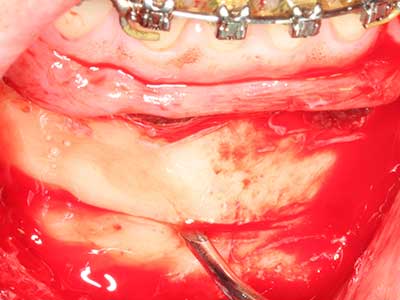

Пиезохирургията има допълнителни предимства при събиране на костни блокове. В допълнение към високата прецизност при остеотомията, описана по-горе, употребата на фините режещи накрайници значително намаляват загубата на материал. Голяма загуба на материал по време на събиране може да се очаква с дебелите накрайници, особено при употреба на борери Линдеман (Lakshmiganthan, Gokulanathan et al. 2012). Базалното разделяне, което е необходимо, особено за присадка на блок при ретромолар, е улеснено от специално създадени правоъгълни триони. В резултат на това, пиезохирургията е разглеждана като прецизна, улеснена и безопасна процедура за събиране на костни блокове в ретромоларното пространство (Happe 2007) (Фиг. 1-12).

Костната тъкан е не само минерализирана структура, тя съдържа и съществено количество колагенови влакна. Това означава, че тя има не само добра компресивна сила, но и известна степен на гъвкавост, която може да се възприеме като предимство при извършване на костна аугментация. В класическата процедура по разширяване чрез костно разделяне, атрофиралият алвеоларен гребен е разделен надлъжно и внимателно разширен след достигане на подходящата остеотомна дълбочина (Фиг. 13-16), в идеалния случай без допълнително отстраняване на периостеума (Brugnami, Caiazzo et al. 2014, Stricker, Fleiner et al. 2014). Системите с винт и пластини с увеличаване на разстоянието при разширяване са доказали ефективността си при разделяне на двете костни ламели, оставайки под прага на фрактурите. В общи линии, оставащата ширина на костта от поне 3–4 mm е задължителна (Chiapasco, Zaniboni et al. 2006), за да се гарантира добра гъвкавост и достатъчно костно покритие за бъдещото поставяне на импланти. Ако е необходимо, вертикалната остеотомия на едната или двете страни може да подобри гъвкавостта. Комбинацията с допълнителни техники за аугментация, особено в букалната страна, е описана като алтернатива на класическата техника.